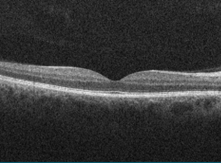

You may also be invited to a special clinic for a scan called OCT (Optical Coherence Tomography). This is a more detailed scan that gives us a 3D image of the back of your eye. It helps us spot problems earlier—especially a condition called diabetic macular oedema (DME), which can affect your central vision.

• It gives a clearer, more detailed view than standard eye photos.

• It helps us spot changes earlier.

• It can reduce the need for hospital referrals.

• It supports faster treatment to help protect your sight.